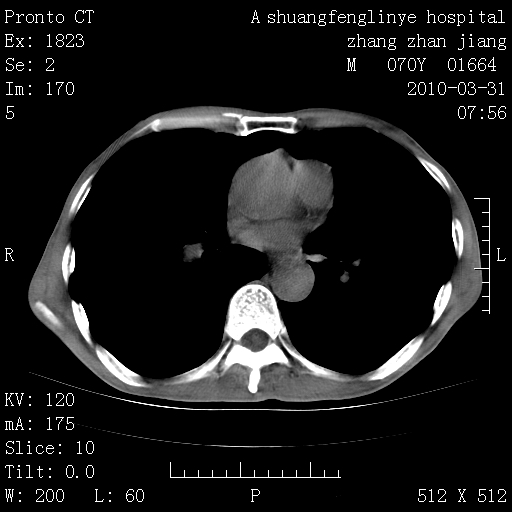

双上肺继发型tb并左上空洞形成,主动脉冠脉钙化。

1)两肺上叶继发性肺结核并左肺上叶空洞形成。2)冠状动脉及主动脉钙化。